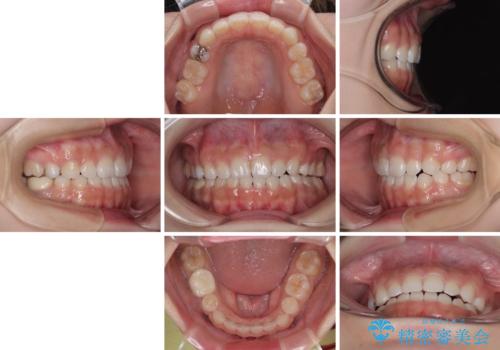

【モニター】デコボコとクロスバイトの前歯 ワイヤー装置での抜歯矯正

- 前歯のクロスバイトと口元の膨らんだ横顔の印象を気にして来院された患者様です。

レントゲン写真の分析結果からは、それほど口元が突出しているという結果にはなりませんでした。

しかしながら、唇を閉じたときに口元に緊張感があり、そのまま叢生を解消すると横顔が突出した印象になる可能性が高かったため、上下左右の小臼歯4本を抜歯して、ワイヤー装置にて矯正治療を行うこととしました。

矯正治療後には、目立っていた奥歯の銀歯をオールセラミッククラウンへ作り替え、スッキリした口元に仕上がりました。